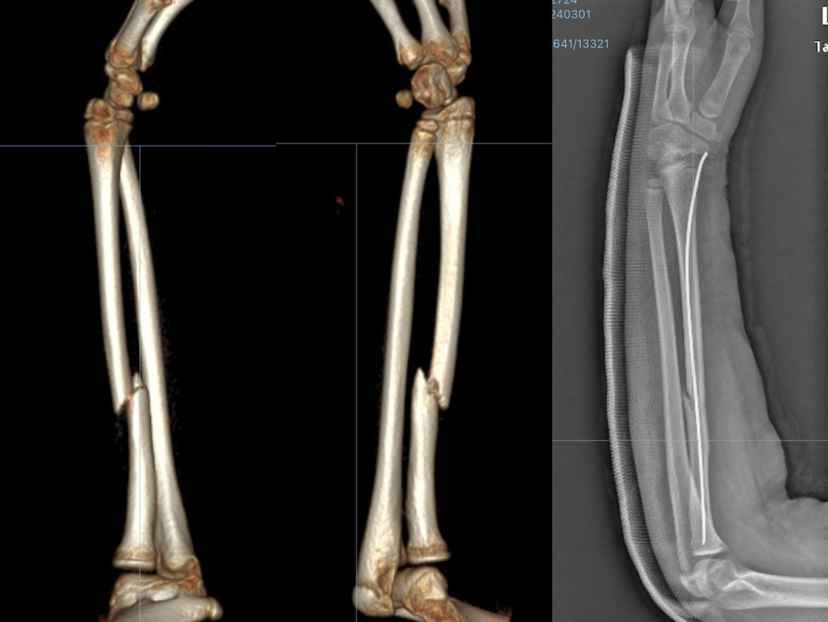

儿童前臂骨干骨折约占儿童骨折6 %,尺、桡骨骨干骨折可分为形变骨折、不完全或青枝骨折和完全移位骨折,对于前两类骨折只需闭合复位石膏托外固定就可以解决,但完全移位的骨折,手法复位常常失败。20世纪70年代,法国南锡的Prevot和Metaizeau介绍了用于治疗无法获得满意对位的不稳定骨折的弹性髓内针固定技术,经过几十年的发展,技术和器械已经十分成熟,在临床上取得显著的疗效。

下面是我主刀的手术病例,有部分与钢板联合使用:

然而,弹性髓内钉治疗也存在一些潜在的感染、髓内针松动等风险,术前医生会根据骨折的类型、位置和严重程度来决定最适宜的治疗方法,术中透视,术后石膏固定,定期复查 X 光,指导功能锻练,避免并发症的发生,经过大量临床实践,治疗儿童前臂骨折首选弹性髓内针技术,安全性高,效果显著。